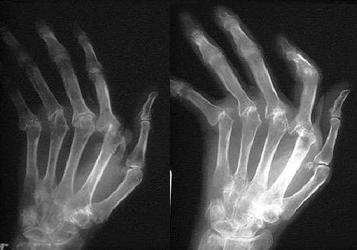

Критерии диагностики ревматоидного артрита Американской ревматологической ассоциации (1987). Наличие по крайней мере 4 из следующих признаков может говорить о наличие заболевания:

- рентгенологические изменения.

Постановка диагноза ревматоидного артрита возможна только при оценке всей совокупности симптомов, рентгенологических признаков и результатов лабораторной диагностики. При положительном результате назначается лечение.